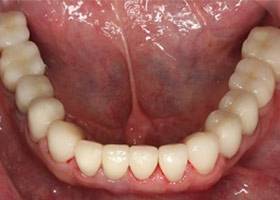

治療後

proimages/case/Artificial_implant/after03.jpg